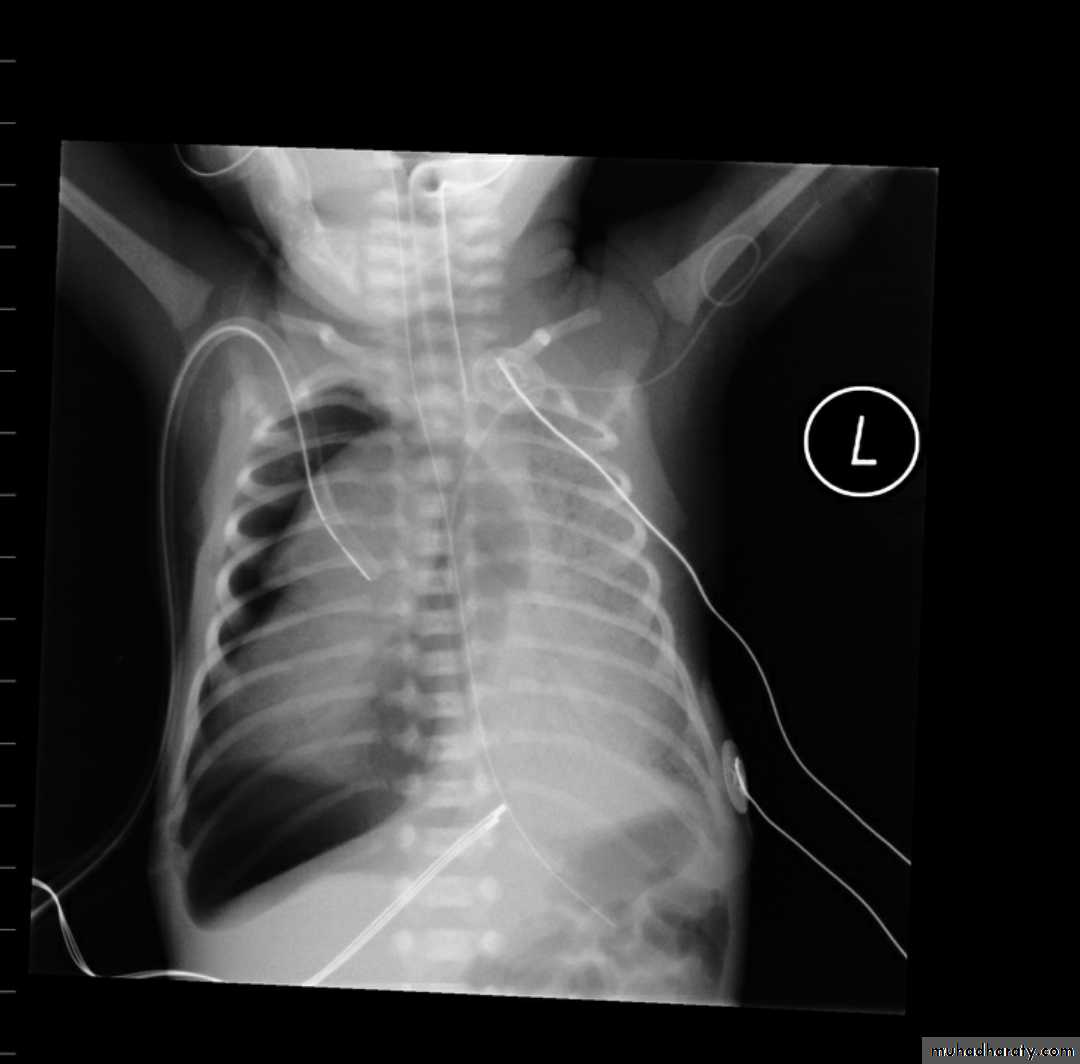

23.normal neonatal chest XR ( normal thymus gland )

24. normal chest XR of the infant( normal thymus gland)

79.Diaphragmatic hernia Vs congenital cystic adenomatous malformation